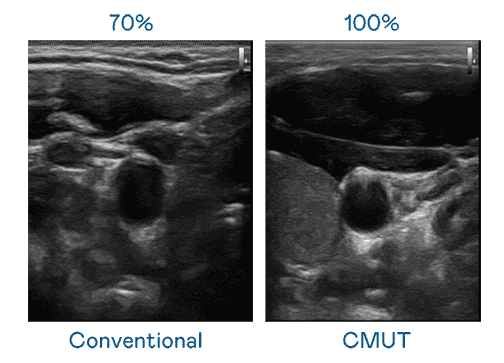

CMUT 技术是一种用电容式微机电元件来产生超音波讯号的技术。。。。与传统 PZT 压电式技术相比,,,CMUT 频宽增加 30%,,,,更宽频的超音波讯号让影像解析度大幅提升,,是实现高影像品质医疗超音波扫描、、促进精准医疗发展的关键技术。。。。

超音波影像的解析度高低,,首先取决于探头能发出的讯号频宽。。。。云顶国际8588yd CMUT 可提供高清晰的超音波讯号,,,,提供高频宽、、高灵敏度、、、、影像纹理细节更高的超音波影像,,,协助医护人员缩短影像判读时间及利用精准的医疗影像进行诊断。。。